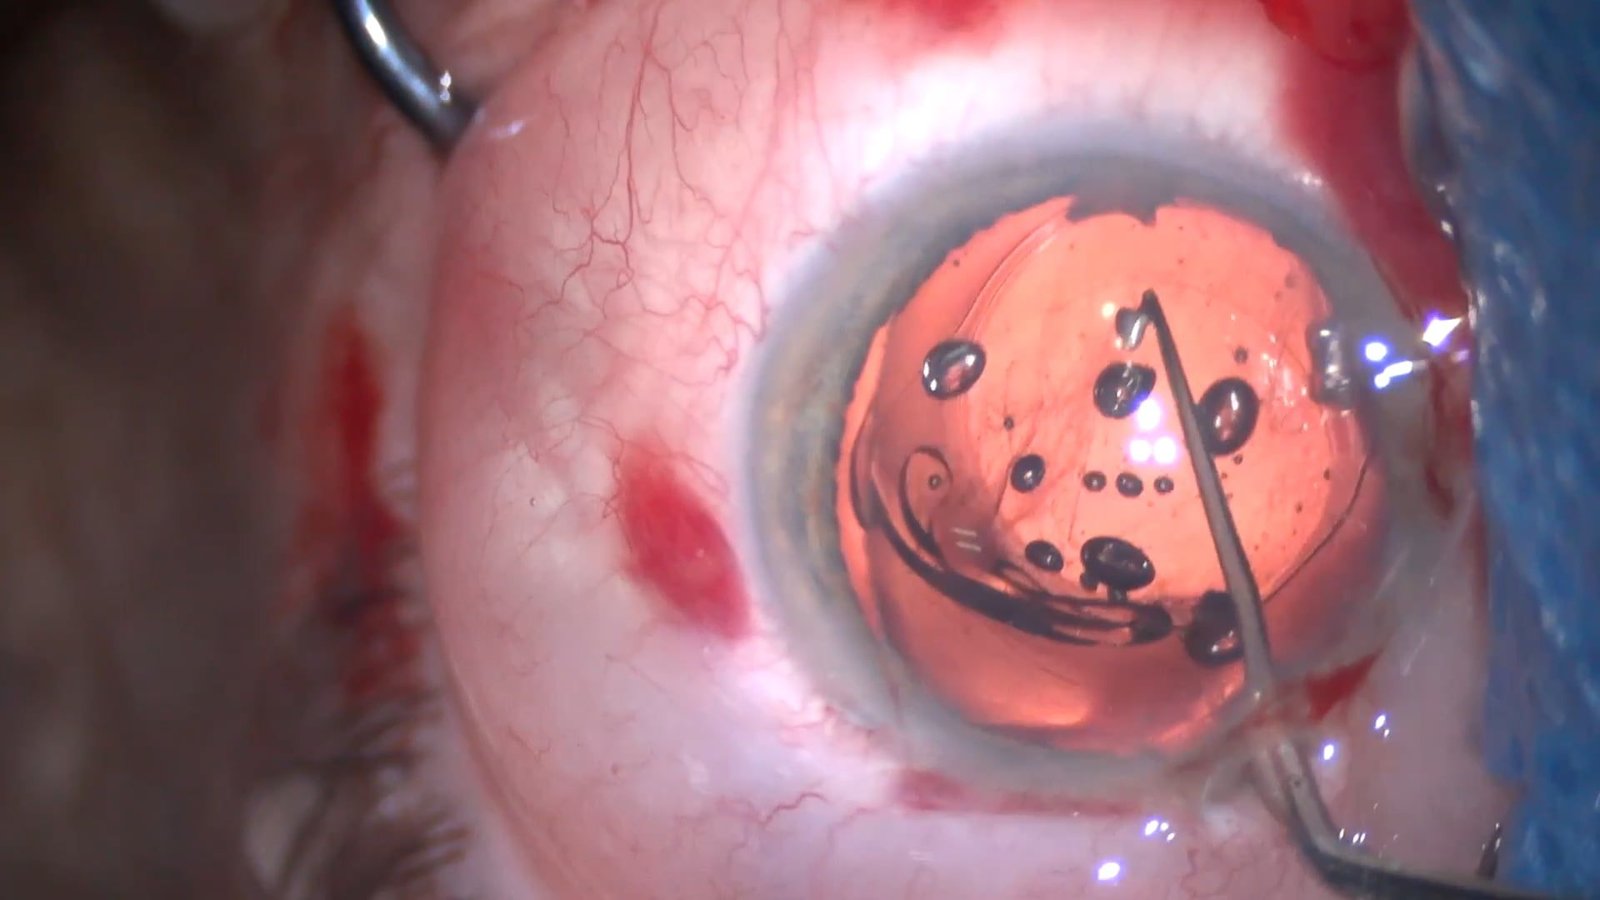

Transfixion of Foldable Intraocular Lens with Pol…

Angel Pineda Fernandez